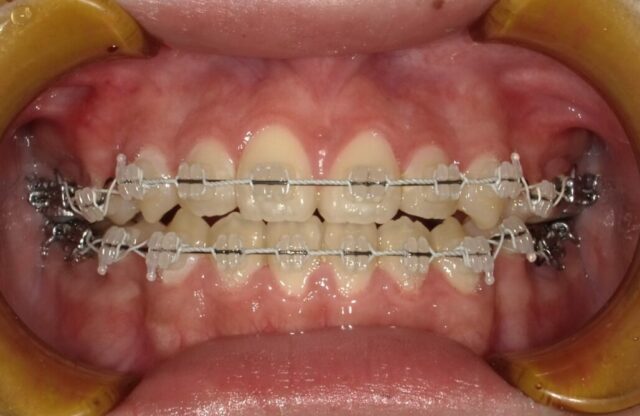

≪正面観≫

2023年5月

2023年6月

2023年7月

2023年8月

2023年9月

2023年10月

2023年11月

2023年12月

2024年1月

2024年2月

2024年3月

2024年4月

2024年5月

2024年6月

2024年7月

2024年8月

2024年9月

2024年10月

2024年12月

2025年1月